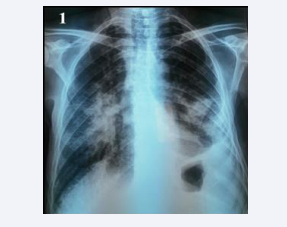

Figure 3 Standard frontal chest X-ray showing bilateral heterogeneous pseudotumour opacities with an appearance of left pleural effusion. Pleural puncture and biopsy revealed tuberculous pleurisy.

Figure 3: Standard frontal chest X-ray showing bilateral heterogeneous pseudotumour opacities with an appearance of left pleural effusion. Pleural puncture and biopsy revealed tuberculous pleurisy.